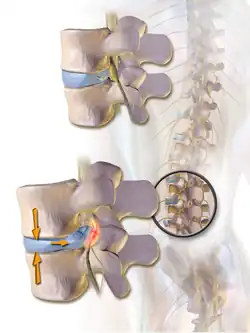

The most common cause of pressure on the spinal cord/nerves is degenerative disc disease.[6] Other common causes include disc herniation, spinal stenosis, trauma, and spinal tumors.[4] Spinal stenosis results from bony growths (osteophytes) or thickened ligaments that cause narrowing of the spinal canal over time.[4] This causes leg pain with increased activity, a condition called neurogenic claudication.[4] Pressure on the nerves as they exit the spinal cord (radiculopathy) causes pain in the area where the nerves originated (leg for lumbar pathology, arm for cervical pathology).[4] In severe cases, this pressure can cause neurologic deficits, like numbness, tingling, bowel/bladder dysfunction, and paralysis.[4]

- Spinal disc herniation